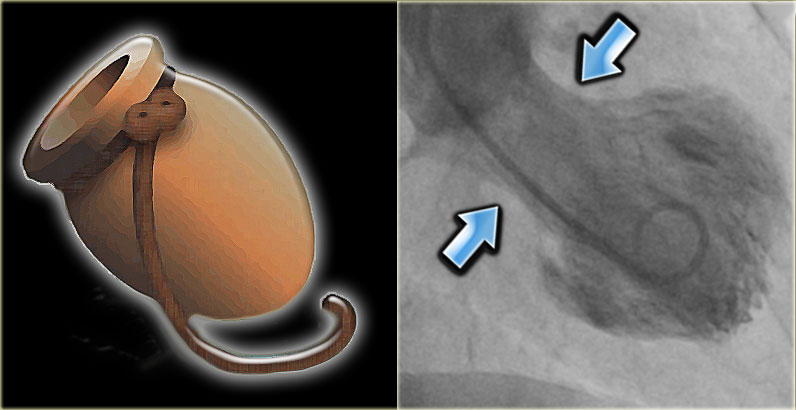

Takotsubo cardiomyopathy is an  unusual response  of the left ventricle to extreme emotional stress .The catecholamine  surge  has  a profound stunning  effect of LV apex  and  a paradoxical hypercontractility of basal LV.

The exact mechanism is not clear , Following factors may contribute.

1. Multi-vessel coronary artery spasm,

2. Cardiac microvascular dysfunction.

3. Abnormal myocardial fatty acid metabolism,

4. Reperfusion injury  after an ACS *

However , the most accepted mechanism is Endogenous catecholamine-induced myocardial stunning and microinfarction

Why is LV apex alone affected  ?

The adrenergic receptor distribution is high in LV apex .They are exposed to high concentration  and gets stunned easily . Basal LV has less adrenergic innervation  , so it shows less of catecholamine toxicity , instead  it exhibits.  hyper-contractile mode. However, this rule is not absolute.

One more suggestion was apical balloons correlated with wrap around LAD.(Báñez B et all 2004)

what is the mechanism of apical ballooning syndrome 2 takotsubo cardiomyopathy

Image courtesy Circulation December 16/23, 2008 vol. 118 no. 25 2754-2762